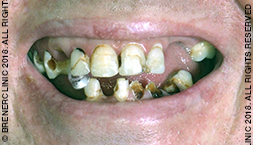

i) Damaged, broken and missing teeth

Step 1 – Diagnosis

Brener Clinic’s aim is to help you make an informed decision regarding your treatment. We begin with a personalised Digital Smile Design consultation to fully understand your needs and to enable us to recommend the ideal treatment options for you.

Importantly, we take into account your goals and desires for your smile before creating an individualised treatment plan for you.